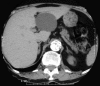

Coral reef aorta (CRA) is described as rock-hard calcifications in the visceral part of the aorta. These heavily calcified plaques grow into the lumen and can cause significant stenoses, which may lead to malperfusion of the lower limbs, visceral ischemia or hypertension due to renal ischemia. From January 1984 to February 2007, 70 patients (24 men, 46 women, mean age 59.5 years, range 14 to 81 years) underwent treatment in the Department of Vascular Surgery and Renal Transplantation, University Hospital, Heinrich-Heine-University (Düsseldorf, Germany) for CRA. The present study is based on a review of patients' records and the prospective follow-up in the outpatient clinic. The most frequent finding was renovascular arterial hypertension (44.3%) causing headache, vertigo and visual symptoms. Intermittent claudication due to peripheral arterial occlusive disease was found in 28 patients (40.0%). Seventeen patients (24.3%) presented with chronic visceral ischemia causing diarrhea, weight loss and abdominal pain. Sixty-nine of the 70 patients (98.6%) underwent surgery; in 57 patients, aortic reconstruction was achieved with thromboendarterectomy, performed on an isolated suprarenal segment in six cases (8.7%), an infrarenal segment in 15 cases (21.7%), and the supra- and infrarenal aorta in 43 cases (62.3%). Eight patients (11.6%) died during or soon after surgery. Postoperative complications requiring corrective surgery occurred in 11 patients (15.9%). Almost one-third of the patients (n=19, 27.5%) returned for follow-up after a mean of 52.6 months (range six to 215 months). Of the 19 patients, there was significant clinical and diagnostic improvement in 16 patients (84.2%) and three patients (15.8%) were unchanged. Impairment was not observed. Despite the existing and improving surgical techniques for the treatment of CRA, its pathophysiological basis and genesis is not yet understood.